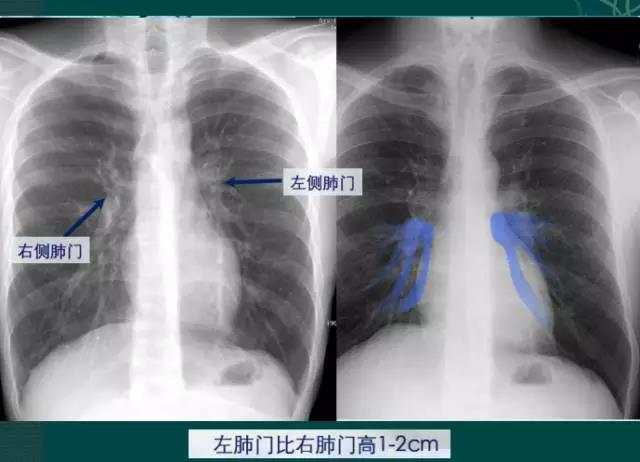

4.肺门的大小和位置

右肺门可分为上、下两部。上部约占1/3,由上肺静脉、上肺动脉及下肺动脉后回归支构成。上肺静脉下后干构成右上肺门的外缘;右肺门下部 约占2/3,由右下肺动脉干构成,其正常宽度不超过15mm,沿中间段支气管外缘平行向外下走行。右肺门上、下部相交形成一钝的夹角,称肺门角,正常该角顶清晰。如下图

左肺门亦分为上、下两部。上部由左肺动脉及其分支、左上叶支气管和左上肺静脉及其分支构成;下部由左下肺动脉及其分支构成,常被心影所遮盖。